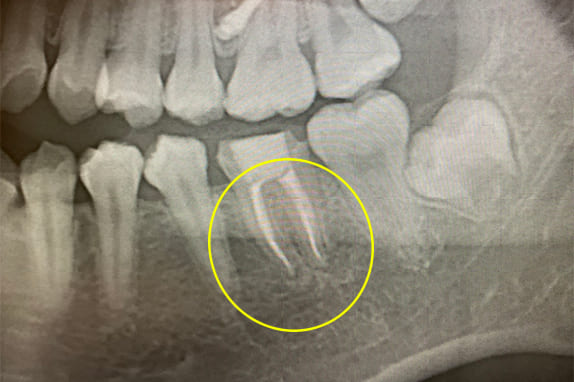

右下の第2大臼歯の咬合痛(噛むと痛む)と歯の揺れを主訴にいらした患者さん。左側術前レントゲン検査では、歯根周囲に黒く影が有り、骨が溶けている状態です。歯の揺れも大きく、他医院で抜歯してインプラントと伝えられ、当院にセカンドオピニオンでいらっしゃいました。

マイクロエンドにより抜歯を回避でき、被せ物までの治療回数は5回。その後揺れも全く無くなり、何でも噛める様になりました。左が根管治療前、右がマイクロエンド1年後のレントゲン写真です。歯根周囲の骨は再生し、黒い影は無くなっています。